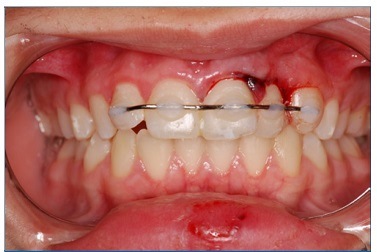

The clinical procedures are summarized in chronological order in Table 1. Firstly, under local anesthesia with 2% lidocaine with 1:100,000 epinephrine (Nova DFL, Rio de Janeiro, Brazil), surgical reduction of teeth 21 and 22 was performed (Figure 4). Subsequently, semi‑rigid splitting of teeth 12‑23 was performed with a 0.4‑mm

orthodontic steel wire (Orthometric, Marilia/SP, Brazil) and composite resin (Z100, 3M, Sumare/SP, Brazil) (Figure 4).